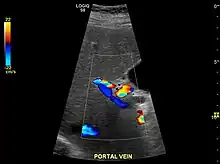

Ultrasound is routinely used in the evaluation of cirrhosis.[35] It may show a small and shrunken liver in advanced disease. On ultrasound, there is increased echogenicity with irregular appearing areas.[52] Other suggestive findings are an enlarged caudate lobe, widening of the fissures and enlargement of the spleen.[53] An enlarged spleen, which normally measures less than 11–12 cm (4.3–4.7 in) in adults, may suggest underlying portal hypertension.[54] Ultrasound may also screen for hepatocellular carcinoma and portal hypertension.[35] This is done by assessing flow in the hepatic vein.[55] An increased portal vein pulsatility may be seen. However, this may be a sign of elevated right atrial pressure.[56] Portal vein pulsatility are usually measured by a pulsatility indices (PI).[55] A number above a certain values indicates cirrhosis (see table below).

| Index | Calculation | Cutoff |

| Average-based | (Max – Min) / Average[55] | 0.5[55] |

| Max-relative | (Max – Min) / Max[57] | 0.5[57][58]–0.54[58] |